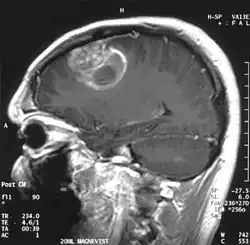

A tomografia computadorizada (TC) e a ressonância magnética (RM) podem detectar efetivamente uma neoplasia no cérebro. A RM é mais sensível que a TC para identificar lesões, mas contraindicações para pacientes com marcapasso cardíaco, próteses incompatíveis, clipes metálicos e outros. A TC continua sendo o método de escolha para detectar calcificações dentro de lesões ou erosões ósseas da calota craniana ou da base. A utilização de agentes de contraste, que são iodados no caso da TC e paramagnéticos ( gadolínio ) no caso da RM, permite a aquisição de informações sobre a vascularização e integridade da barreira hematoencefálica, uma melhor definição do tumor tumoral comparado ao edema circundante e à geração de hipóteses sobre o grau de malignidade . O exame radiológico também permite avaliar os efeitos mecânicos e consequentes alterações nas estruturas cerebrais decorrentes do tumor, como hidrocefalia e hérnias, cujos efeitos podem ser fatais. Finalmente, na preparação para a cirurgia, esse diagnóstico pode ser usado para determinar a localização da lesão ou a infiltração do tumor em áreas vitais do cérebro. Para isso, a RM é mais eficiente que a TC, pois pode fornecer imagens tridimensionais.

Na ressonância magnética, um tumor intracraniano aparece como uma lesão maciça que pode se tornar mais luminescente após o uso do agente de contraste. No entanto, há sempre uma anomalia de sinal na ressonância magnética, que indica a presença de neoplasia ou edema vasogênico. Normalmente, o aumento da luminescência (realce pelo contraste) é indicativo de um tumor de grau mais alto de malignidade. Um anel contrastante é característico do glioblastoma, com a porção luminescente correspondendo à parte vital do tumor maligno e a área mais escura-hipointense à necrose tecidual.

As metástases cerebrais são as neoplasias intracranianas mais comuns em adultos, sendo dez vezes mais comuns que os tumores cerebrais primários. Eles pisam em 20 até 40 por cento dos adultos com câncer e estão associados principalmente ao câncer de pulmão e mama e melanoma . Essas lesões resultam da disseminação de células cancerígenas pela corrente sanguínea e ocorrem mais comumente na junção da substância cinzenta e branca, onde a seção transversal dos vasos sanguíneos se altera, aprisionando embolias de células tumorais . 80 por cento das lesões ocorrem nos hemisférios cerebrais, 15 por cento no cerebelo e 5 por cento no tronco cerebral. Cerca de 80 por cento dos pacientes têm história de câncer sistêmico e 70 por cento têm múltiplas metástases cerebrais.

Avanços significativos foram feitos recentemente no diagnóstico e tratamento dessas lesões, resultando em melhora da sobrevida e controle dos sintomas. O início dos sinais e sintomas é semelhante ao de outras lesões maciças no cérebro. O método diagnóstico de escolha é a ressonância magnética com meio de contraste.